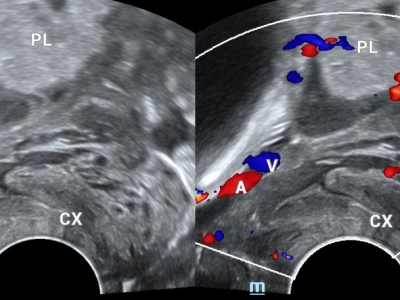

【健康科普】前置血管:胎儿生命通道的隐形杀手